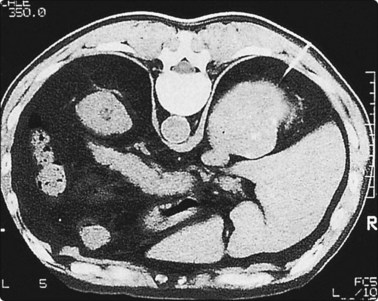

Localization of the needle tip within a lesion is very accurate with CT (Fig. 3.3). It provides detailed cross-sectional images of the body which are not limited by the same physical properties as are ultrasound images, such as interference from bowel gas and bone.

image

Fig. 3.3 Inflammatory lesion of the lung

Tissue is obtained for culture and other appropriate tests. Local anaesthetic is visible in the subcutaneous tissues.